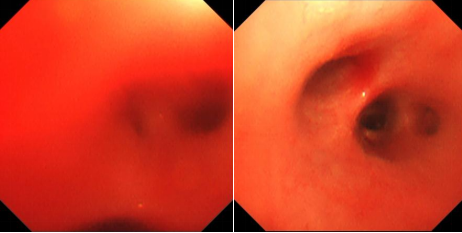

PICU 团队仔细了解了小 U 的病情,觉得小 U 的病并不简单。经过一系列的检查,发现小 U 为急性重度失血性贫血,CT 提示出血灶在肺部,经过电子支气管镜探查后,发现小 U 为弥漫性肺泡出血,多学科会诊后考虑特发性肺含铁血黄素沉着症可能性大,小 U 的肺泡灌洗液铁染色检查为阳性,可见含铁血黄素吞噬细胞,最后确诊了该病。经过积极对症治疗,小 U 转危为安,肺出血止住了,顺利转出至普通病房。

特发性肺含铁血黄素沉着症的诊断主要根据缺铁性贫血、呼吸道症状、影像学提示浸润性表现,在胃液、痰液、支气管肺泡灌洗液或肺活检组织中找到含铁血黄素细胞,并排出其他引起肺出血的原因。